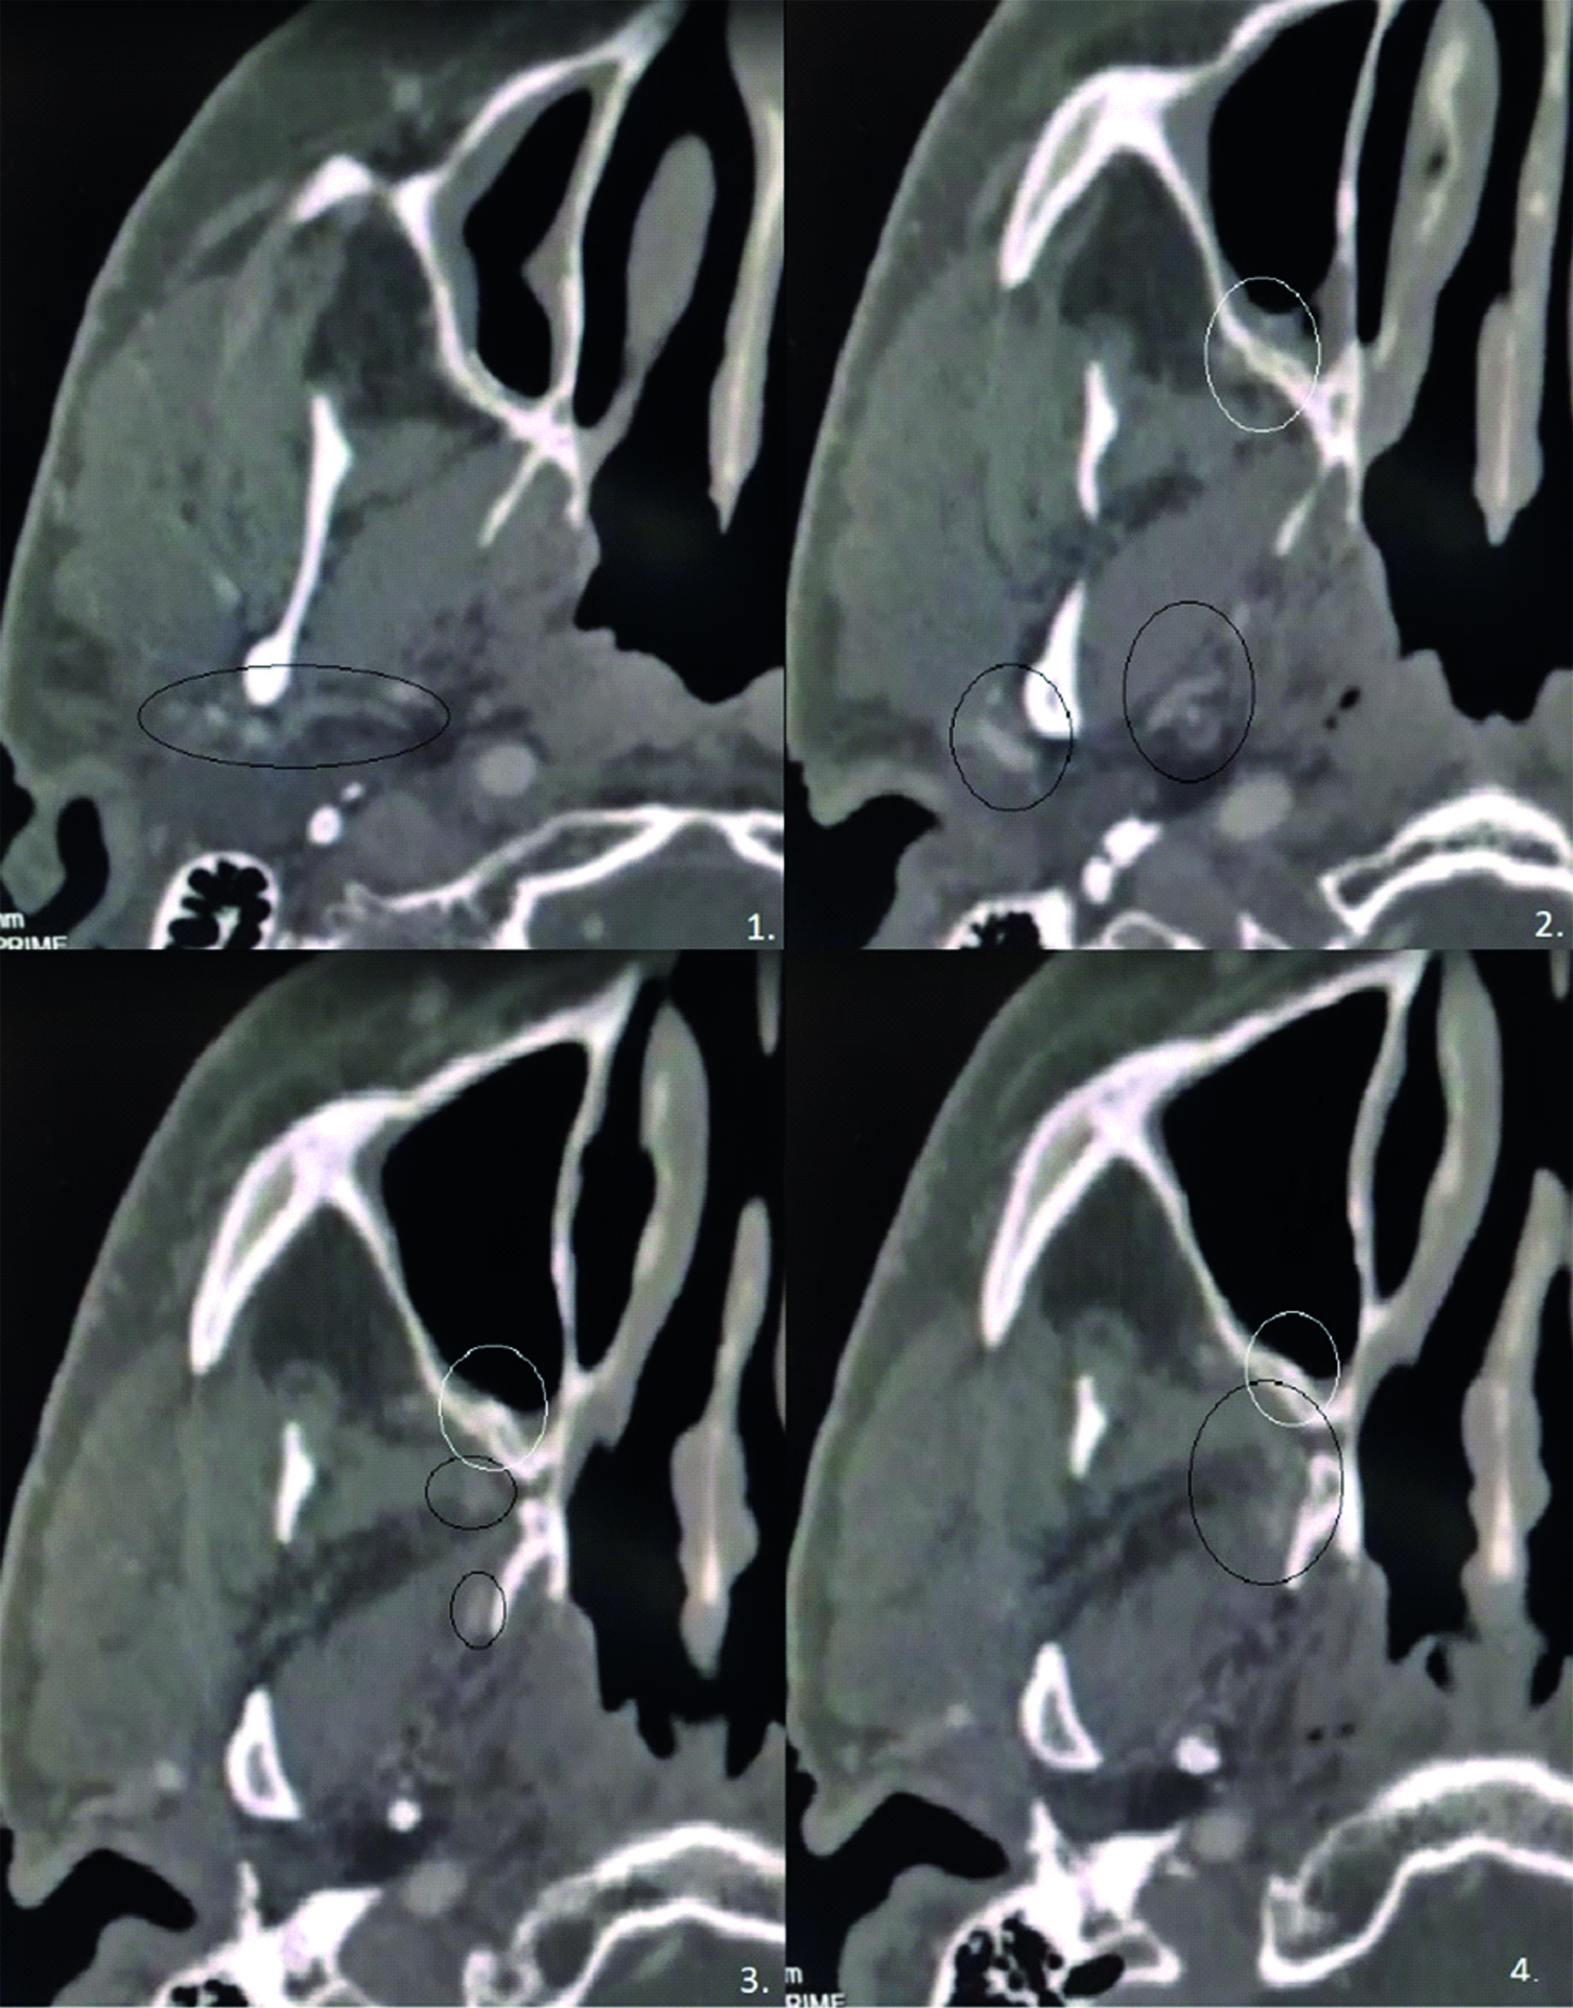

05.07.2021 выполнено повторное КТ ОНП с контрастом для визуализации эмболизированной a. maxillaris и контроля отдаленных результатов операции. На КТ ОНП – визуализирована верхнечелюстная артерия, не вдающаяся в верхнечелюстную пазуху, прилегающая к ее задней стенке. Дефект верхнечелюстной пазухи отсутствует, визуализируется костная мозоль (рисунок 4).

Рисунок 4. КТ околоносовых пазух от 05.07.2021 с контрастом. Белым кругом обозначено бывшее расположение дефекта задней стенки верхнечелюстной пазухи, через которое аневризма верхнечелюстной артерии выходила в полость верхнечелюстной пазухи. Черным кругом обозначен ход верхнечелюстной артерии. Снимки выполнены с введением контраста на 23 секунде.

Figure 4. CT imaging of the paranasal sinuses with contrast dated 07.05.2021. The white circle indicates the former location of the defect in the posterior wall of the maxillary sinus, through which the aneurysm of the maxillary artery entered the cavity of the maxillary sinus. The black circle indicates the course of the maxillary artery. The pictures were taken using the contrast at 23 seconds.